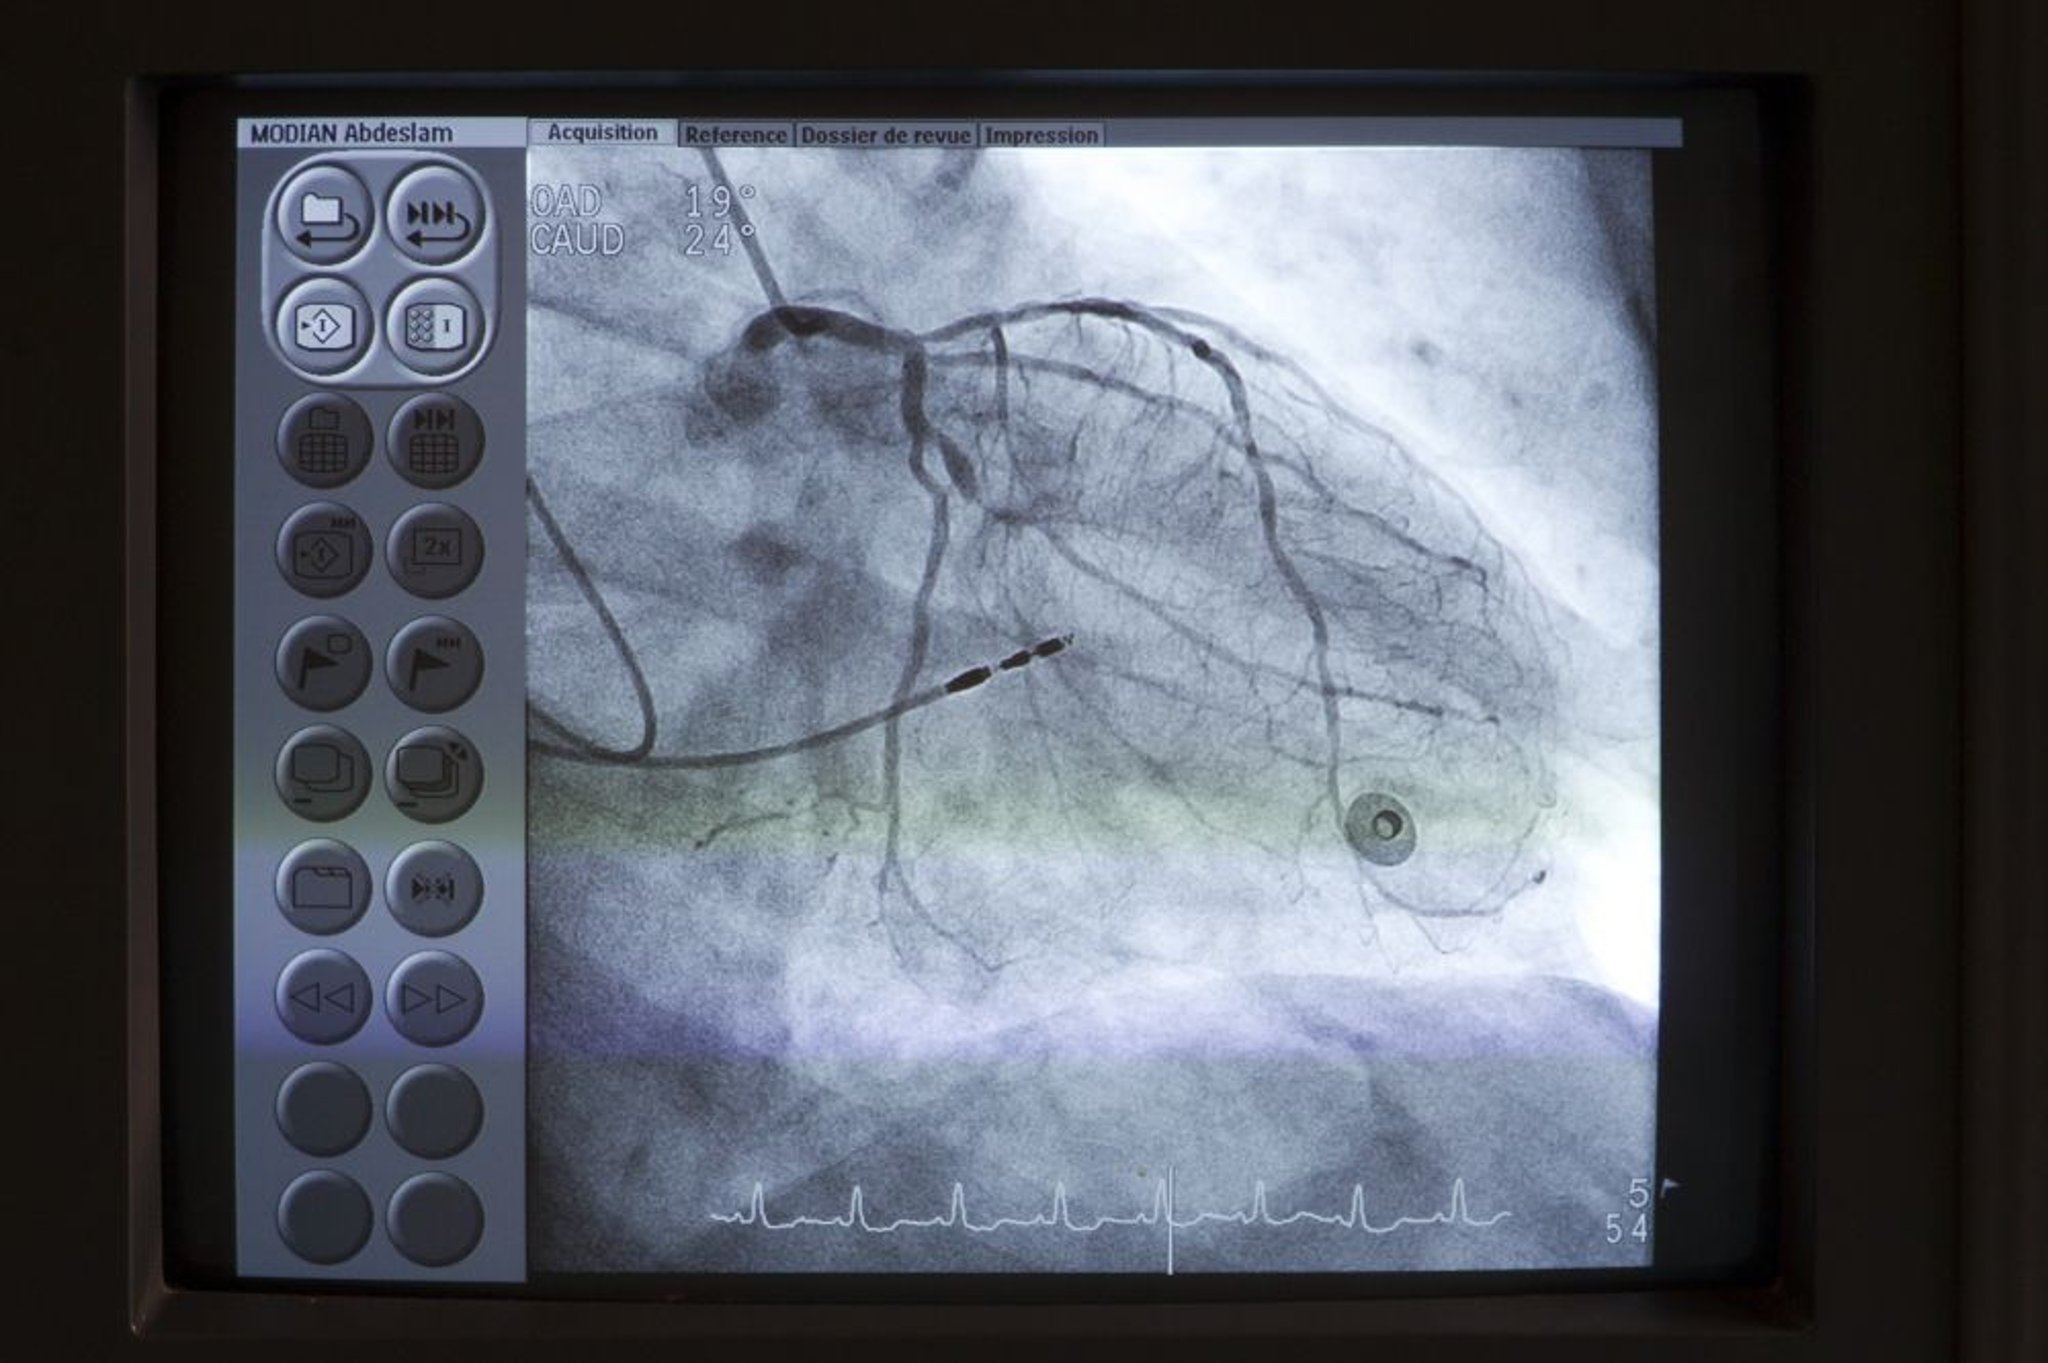

Angiografía coronaria

Se coloca un catéter (arriba a la izquierda) en el origen de la arteria coronaria principal izquierda. Luego se inyecta el medio de contraste en las arterias coronas bajo fluoroscopia para detectar anomalías como estenosis.

Astier/BSIP/SCIENCE PHOTO LIBRARY